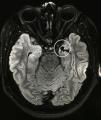

Materials and methodsEight paediatric patients met strict criteria for IND and were enrolled in this study. Electroencephalography (EEG), video electroencephalography (VEEG) and magnetic resonance imaging (MRI) were performed in all patients prior to surgery. Irreducible neuroagressive symptom was approached by lesional therapy based on most described targets for this disorder and assessed by the Overt Aggression Scale (OAS) pre-operatively and 6 months following surgery, using Wilcoxon test for statistical analysis.

Results and conclusionsThe average patient age was 13 years 2 months. 7 of the 8 patients enrolled had intellectual disabilities, 1 patient suffered neurologic sequelae referable to Dandy–Walker syndrome and 7 patients had no preoperative anatomical alterations. Following surgery, patients with IND noted improvement in their OAS. On average, the OAS improved by 39.29% (p=.0156), a figure similar in comparison to studies assessing treatment of IND in adult patients. The most satisfactory results were achieved in patients whose ablative therapy involved the Amygdala in their targets. There were no deaths or permanent neurological deficits attributable to procedure. To the author's knowledge, this is the largest series described in the literature for paediatric patients with IND treated with lesional stereotactic therapy.